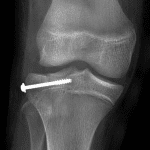

Age: 11

Sex: Female

Indication: Knee injury

Sample ReportAcute minimally depressed Salter IV fracture of the lateral tibial plateau. No physeal widening.

Large joint effusion.

No joint malalignment.